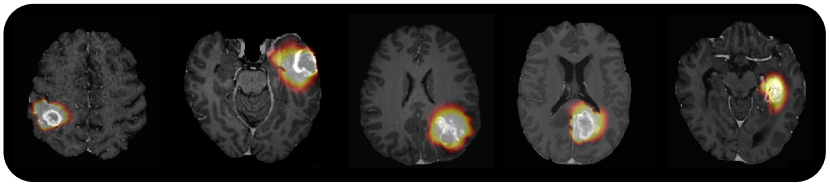

Solving the inverse problem is the key step in evaluating the capacity of a physical model to describe real phenomena. In medical image computing, it aligns with the classical theme of image-based model personalization. Traditionally, a solution to the problem is obtained by performing either sampling or variational inference based methods. Both approaches aim to identify a set of free physical model parameters that results in a simulation best matching an empirical observation. When applied to brain tumor modeling, one of the instances of image-based model personalization in medical image computing, the overarching drawback of the methods is the time complexity for finding such a set. In a clinical setting with limited time between imaging and diagnosis or even intervention, this time complexity may prove critical. As the history of quantitative science is the history of compression [1], we align in this paper with the historical tendency and propose a method compressing complex traditional strategies for solving an inverse problem into a simple database query task. We evaluated different ways of performing the database query task assessing the trade-off between accuracy and execution time. On the exemplary task of brain tumor growth modeling, we prove that the proposed method achieves one order speed-up compared to existing approaches for solving the inverse problem. The resulting compute time offers critical means for relying on more complex and, hence, realistic models, for integrating image preprocessing and inverse modeling even deeper, or for implementing the current model into a clinical workflow.

In this paper, we propose an image retrieval based approach that performs a query of patient specific scans to a database of synthetic tumors, returning the closest resemblance of the patient’s tumor. As a baseline, this image retrieval process is implemented via a primitive iterative pair-wise comparison. Further, we investigate how a retrieval in low dimensional embeddings of the simulations – that we obtain by using downsampling as well as autoencoders, variational autoencoders, unsupervised hashing, and radiomics feature representation – can improve runtimes. As a result, our work shows that our query approach can yield accurate and, depending on the chosen optimization, also deterministic results in the order of seconds (correspondingly, minutes for the inverse problem).

Here we want to discuss the pros and cons of the proposed method. First, the method is deterministic - it relies on direct computation of the best match among tens of thousands of precomputed simulations under the measure of interest. Even though we provided a comparison with different query strategies analysing the trade-off between accuracy and time, by using the direct query strategy one obtains ”global optimum” for the query at an acceptable runtime, so we suggest to use it in practice. Also despite using the DICE score as such a measure (since it is the first metric of choice in our community), the method is evidently generalizable to any arbitrary measure. The overall runtimes for the solving the inverse problem, including registration, query, and back transform vary from two (for the inaccurate RF query) to eight minutes (for the optimal direct query). This is an order of magnitude faster than any existing brain tumor inverse problem solving methods (starting from ca. 1 hour for the same resolution by [6, 7]). One may question whether such a speed-up comes at the cost of a significant error, which in turn comes from the registration to and finding the best matching in the atlas space. While we would agree with such a statement, it is worth to mention that dominant majority of existing literature resorts to such atlas registration in order to approximate the patient specific anatomy.

We present a method for inferring a tumor simulation from information available on medical scans relying on a simple database query strategy. A reader might say that the proposed method is a joke due to its offensively simple nature. While we would again agree with such a statement, we do believe that the method provides a generalizable, fast, and robust solution to the inverse problem. The runtimes for solving the inverse problem are in the order of a few minutes which is faster than any existing inverse modeling method. Even though the used database is composed of simulations from the reaction-diffusion model that might not be sufficient to provide a close match to real tumor growth in general, it is evident that the proposed method is generalizable to more sophisticated models (one just needs to resimulate tumor database in the atlas space with more complicated tumor model). As opposed to data-driven approaches, the method does not fail at extrapolation as it is based on a plain compute of the overlap measure between two binary volumes.